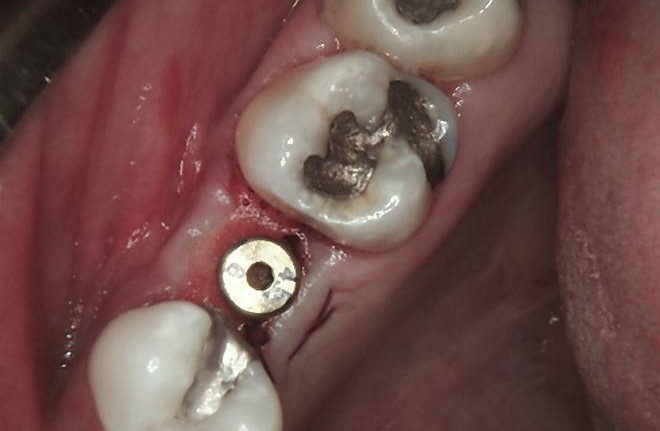

HEALING STAGE

During the healing phase, soft tissue maturation and integration were closely monitored. Soft tissues were carefully managed, using the Free Gingival Graft technique, which allowed for enhancing keratinised tissue and improving peri-implant tissue stability.

A healing cap was placed to guide soft-tissue contouring and support optimal formation of the emergence profile.